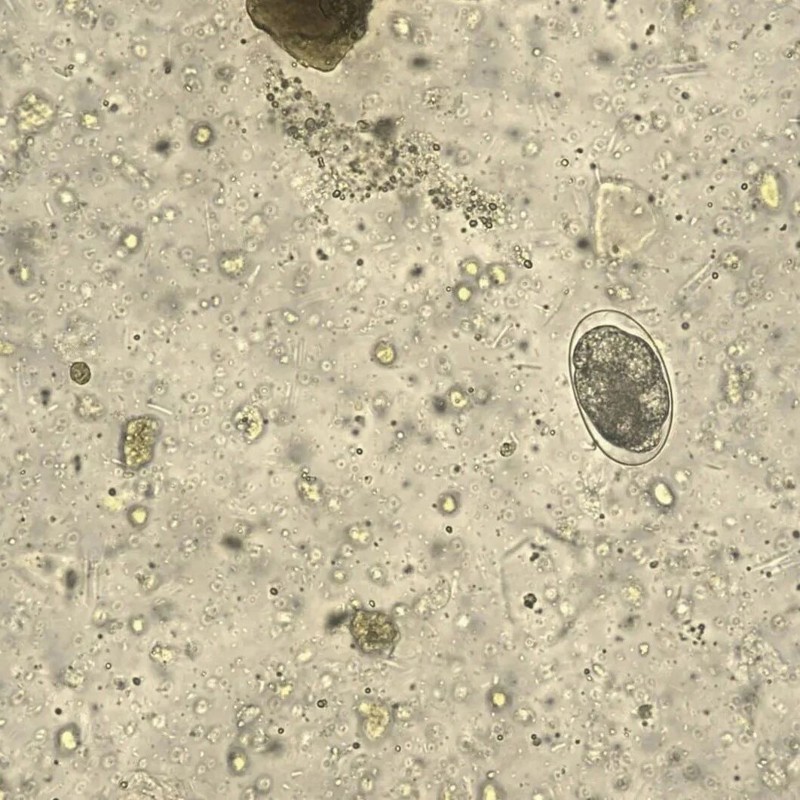

从矛盾到真相:一例血尿酸正常的痛风性关节炎诊断分析